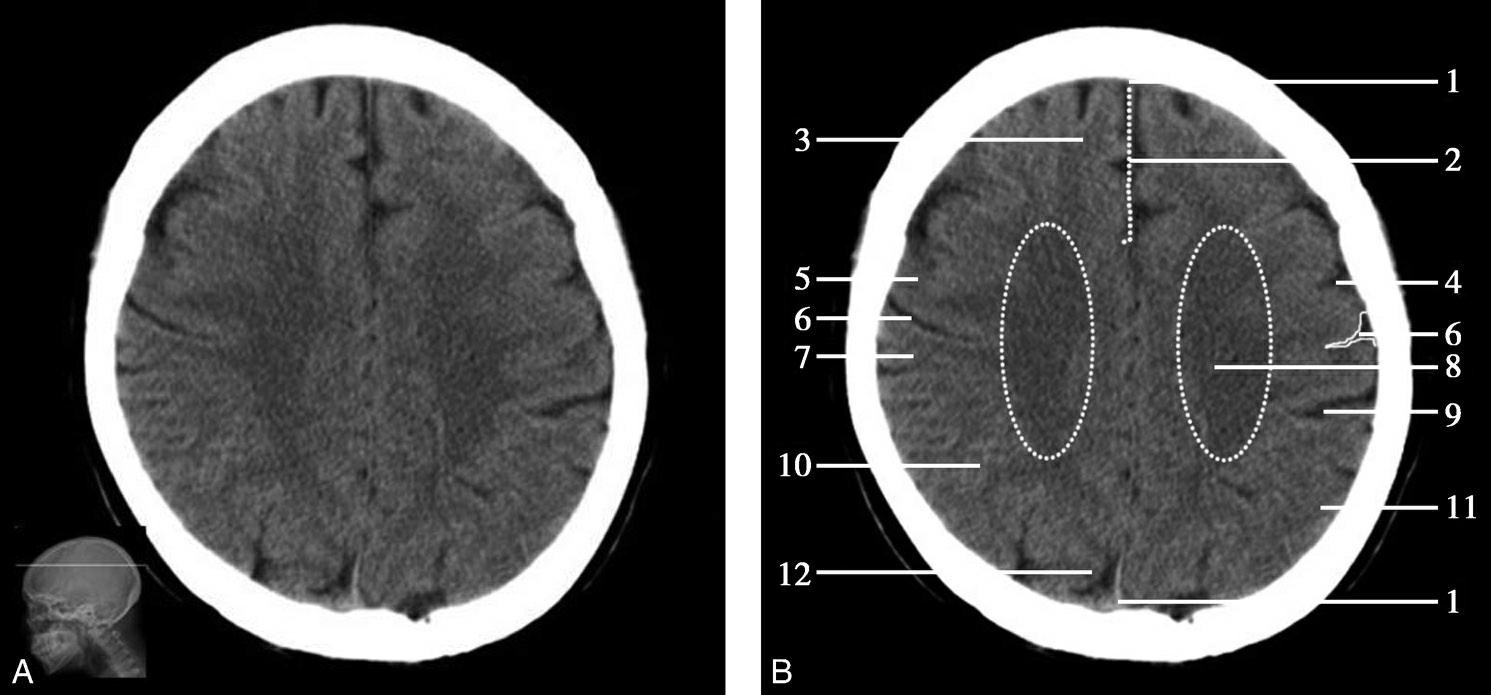

Alberta卒中项目早期CT评分(Alberta stroke program early CT score,ASPECTS)是一种评价急性缺血性卒中患者大脑中动脉供血区早期缺血性改变的简单、可靠、系统化的方法,是常用的脑卒中评定量表之一,可对缺血性病变快速进行半定量评价,有助于判定溶栓效果和远期预后。该评分主要基于CT平扫,具体分区如下(图1-2-76)所示,即选取大脑中动脉供血区2个层面。分区后共10个区域,每个区域记1分。评分时任何区域只要有低密度灶,则扣除该区域得分。正常脑ASPECTS评分为满分(10分),若MCA供血区广泛梗死累及全部区域时,则ASPECTS评分为0分。

图1-2-76 ASPECTS评分脑组织分区

A.在基底节层面(即丘脑和纹状体平面),分为各级分支M 1 、M 2 、M 3 、岛叶(缩写I)、豆状核(缩写L)、尾状核(缩写C)和内囊(缩写IC)后肢等7个区域;B.在基底节以上层面(基底节层面上2cm),包括M 4 、M 5 和M 6 。